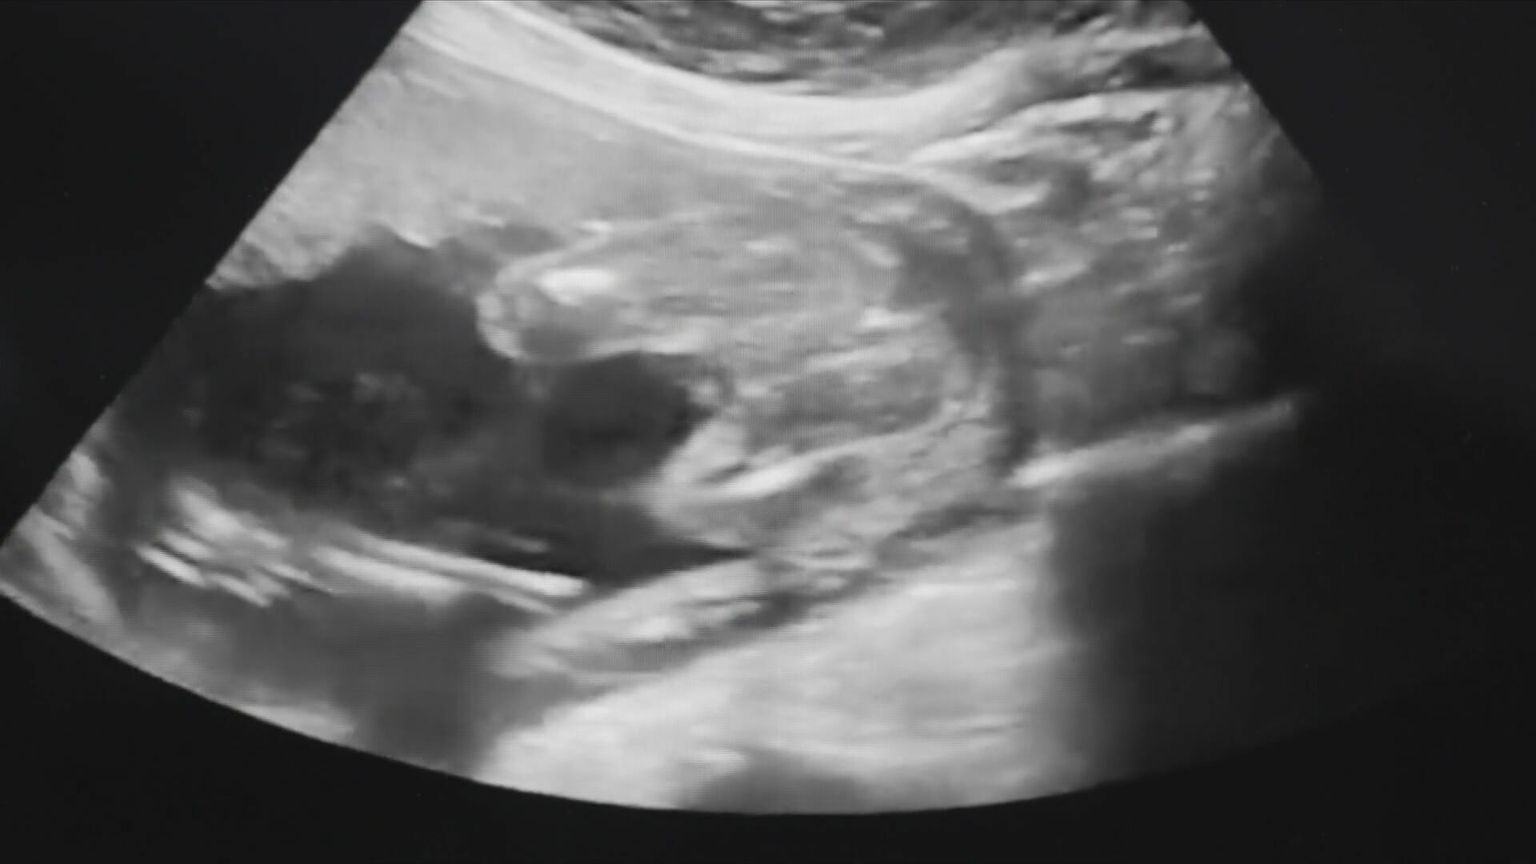

Djevojka kojoj je u KBC-u Osijek izveden neuspjeli pobačaj progovorila za Dnevnik Nove TV i kaže - tužit će bolnicu

• Neuspio pobačaj - 2 Foto: DNEVNIK.hr